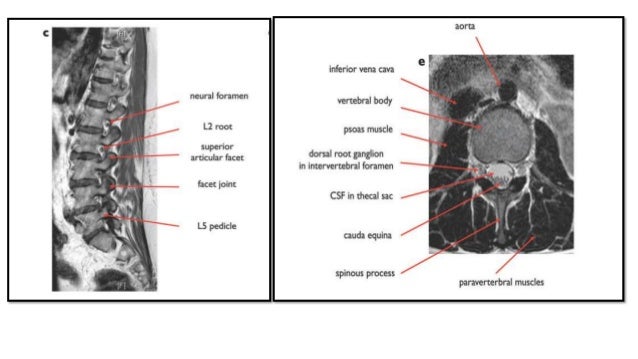

Magnetic resonance imaging (mri) of the spine uses radio waves, a magnetic field and a computer. Dentate ligament (anchors the spinal cord in position). The spine is composed of multiple vertebrae, which protect the.

Further imaging with ct or mri (not discussed) is often appropriate in the context of a high risk injury, neurological deficit, limited clinical examination tap on/off image to show/hide findings. Athletic injuries to the head, neck, and face. Anatomy for diagnostic imaging 2e. Imaging should provide enough anatomic coverage to detect transitional anatomy at the lumbosacral junction.